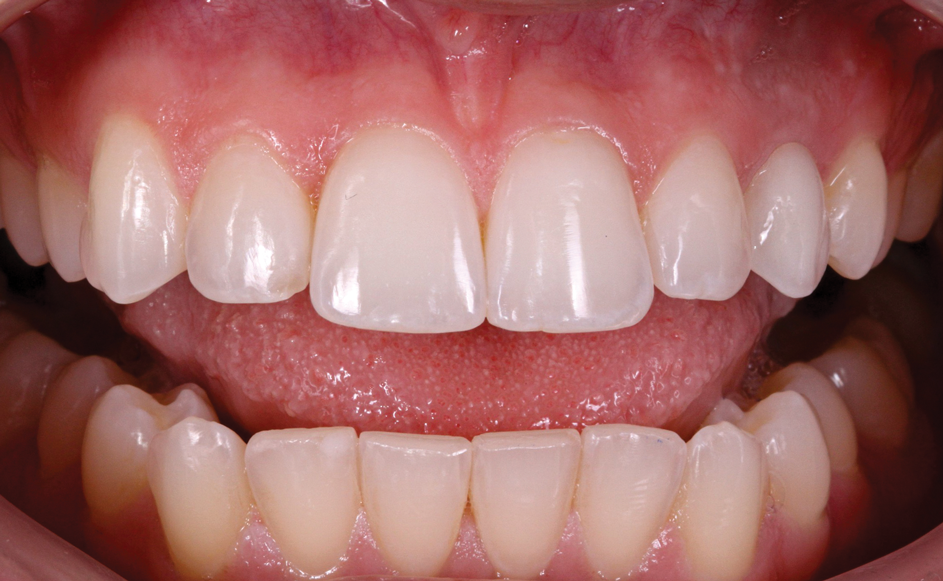

(33.) Retracted view with the teeth apart and close-up view of the definitive screw-retained zirconia restoration in position (Definitive restoration fabricated by Sam Alawie and Beverly Hills Dental Lab).

Figure 33

(34.) Retracted view with the teeth apart and close-up view of the definitive screw-retained zirconia restoration in position (Definitive restoration fabricated by Sam Alawie and Beverly Hills Dental Lab).

Figure 34